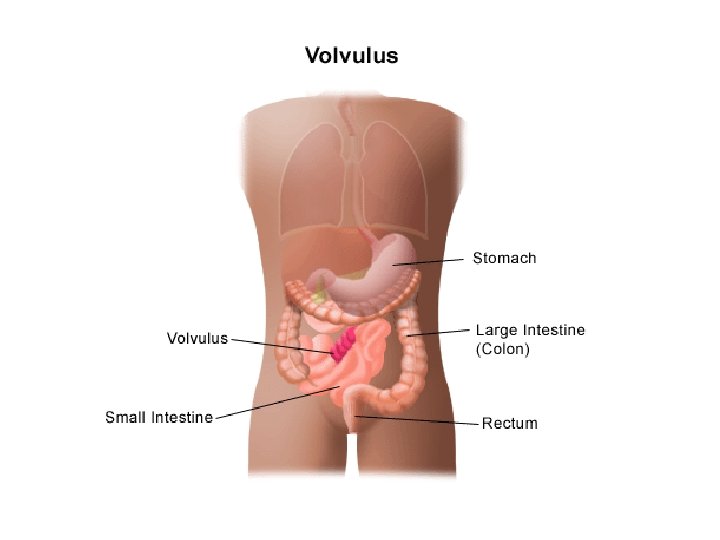

OKLUZIONET INTESTINALE

• Okluzioni Intesitnal ( Ileusi) OI eshte mos eliminimi i transitit te materialeve fekale , tretesirave digjestive e te gazrave nga pengesa te ndryshme mekanike ose parelitike.

• Okluzioni mekanik vjen nga patologji qe kane origjinen ne lumenin e zorres, ne murin e saj dhe strukturat indore fqinje. • Okluzioni intestinal nga strangulacioni shoqerohet edhe me bllokimi te menjehershem te eneve te gjakut dhe me nderprerjen e qarkullimit te gjakut.

Volvulus i kolonit sigmoid